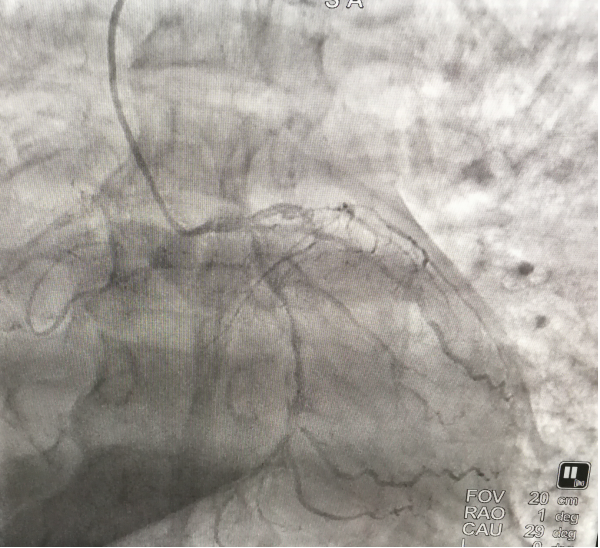

冠脉造影结果显示,患者面临的是极其危险的冠脉三支病变,远端血流受到极大影响,左前降支血管中断闭塞,左回旋支75%-90%的狭窄,右冠状动脉99%的狭窄。蒋小菊在查看造影结果后明确指出,要尽快开通血管。在呼吸机的辅助支持下,心血管内科团队成功为患者闭塞的血管破开道路,顺利完成了救治。